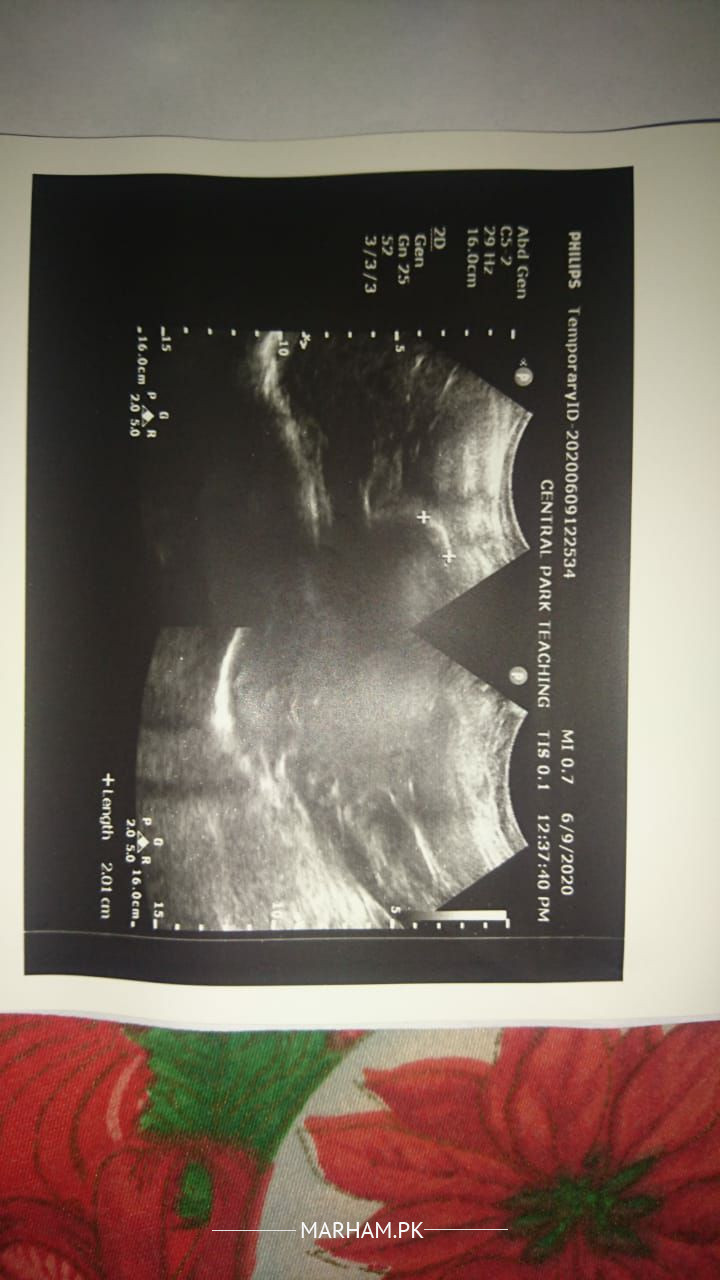

Asking For Mother, Female 50, lahore

Asslam o Alaikum kindly anyone explain these report briefly is this reports ok or not I'm very worried about it. thankyou

The picture is a little blurred.

this abdominal ultrasound shows 3 stones in gallbladder..

rest of the report is fine..

stone in gall bladder

you are having cholilithiasis. yani pittay mai pathri hai.

the stone size is 21 mm which is considerably large and can cause blockage of duct as well.